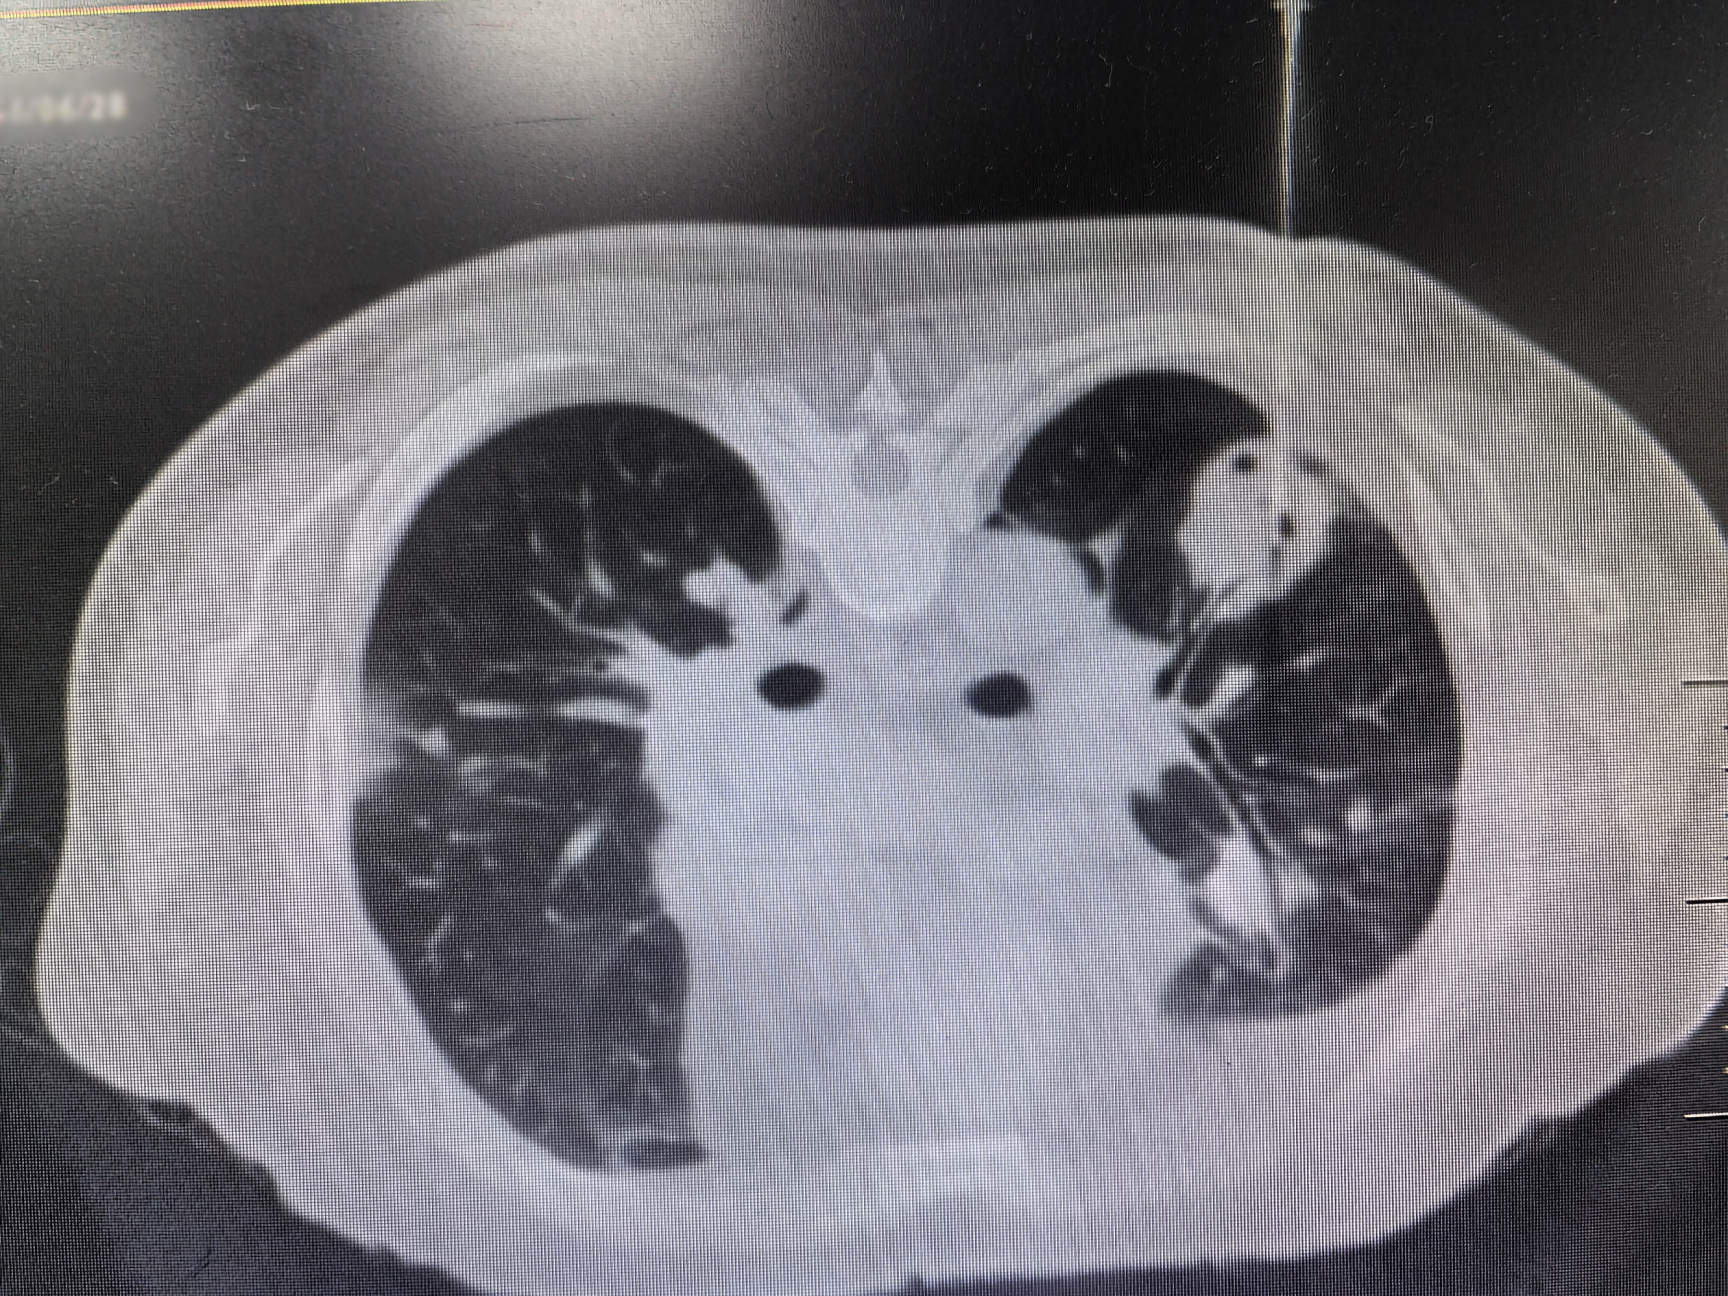

近日,樱花动漫 呼吸介入团队成功为一位双肺多发结节的老年男性患者开展医院首例双肺结节同步穿刺术,为患者明确诊断了“韦格纳肉芽肿病”这一罕见病。

该患者因进行性加重的咳嗽、胸闷、气促,辗转多家医院,进行了多次临床检查及肺结节穿刺活检,均未能明确诊断。患者一度焦虑地表示欲前往广州请钟南山院士诊治。柴燕玲教授接诊后,与科室陆霓虹博士等专家进行了讨论,初步怀疑为罕见的血管炎性疾病-韦格纳肉芽肿病(Wegener’s granulomatosis,WG),其确诊依赖肺活检。

与患者反复沟通病情后,患者最终同意再次进行肺活检。完善术前检查、排除肺活检禁忌证后,在呼吸介入团队医护配合下,陆霓虹博士为患者实施了高难度“双肺结节同步穿刺活检术”。手术仅用时12分钟,顺利获取病变组织,且患者无并发症。病理检查(ROSE)提示肉芽肿性病变,结合血液c-ANCA阳性,最终确诊为“韦格纳肉芽肿病”(WG)。经对症治疗,患者症状显著好转。

韦格纳肉芽肿病(WG)是一种特殊的坏死性肉芽肿性血管炎,病因不明。病变常累及多个器官,病理表现为肉芽肿性病变,伴血管壁炎症。因WG发病率较低,肺部病变常常被误诊为肺部肿瘤或者肺结核。2024年发表的中国肺结节规范化诊疗专家共识指出,双肺多发结节须进行双肺的活检取材,避免结节漏诊及误诊。双肺同步穿刺技术难度较高,对操作医师的熟练程度、操作技术水平均有要求。